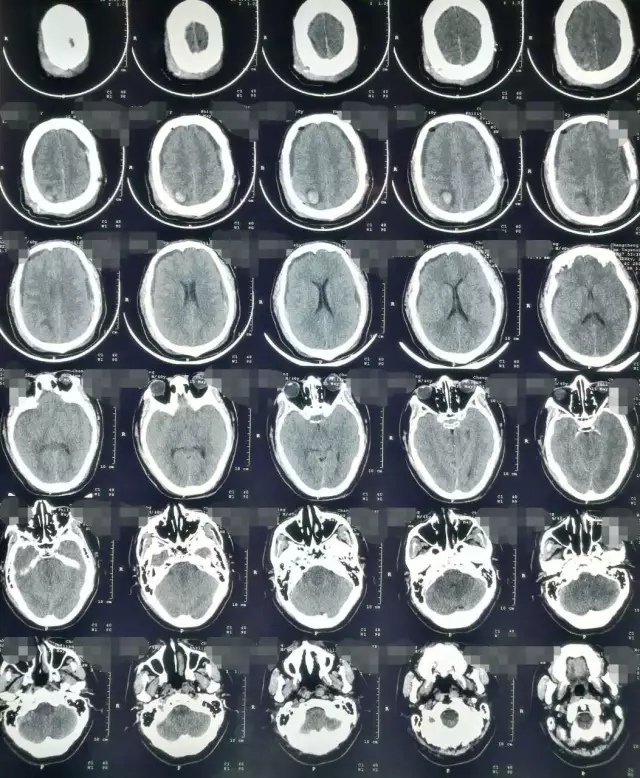

患者,男,40岁;因不明原因反复头痛并加重2月,于2017年4月21日当地医院头颅CT、MRI提示:双侧额颞顶部慢性硬膜下血肿收住院(图1)。并于4月24日行“左侧慢性硬膜下血肿钻孔引流术”。术后患者卧床、静脉补液,头痛症状有所缓解。复查头颅CT显示左侧血肿较前减少,但右侧稍增大(图2)。

图1. 第一次术前CT及MRI显示双侧慢性硬膜下血肿,中线稍右偏。